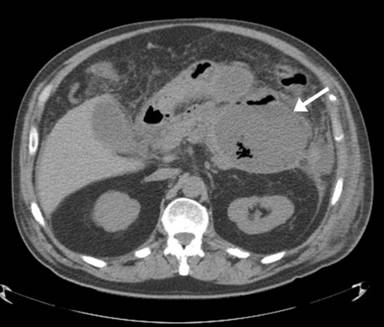

A CT abdomen and pelvis was obtained which showed inflammation about the pancreas and a very prominent 9.0x9.3 cm pseudocyst with air-fluid levels in the tail of pancreas (Figure 1). A smaller air-filled fluid collection was seen in head of pancreas too. In addition, moderate left sided pleural effusion was also present. A diagnosis of infected necrotizing pancreatitis with fluid collection was made. Empiric coverage with piperacillin-tazobactam was started. Warfarin coagulopathy was reversed with fresh frozen plasma. Hemodialysis and total parenteral nutrition was then initiated. CT guided drainage of pancreatic pseudocyst drained 330 mL of purulent cloudy fluid which was sent for analysis. Gram stain of pseudocyst revealed beaded gram positive rods. Acid fast bacillus and fungal cultures were negative. Antibiotics were now changed to penicillin and trimethoprim/sulfamethoxazole for presumptive actinomyces and/or nocardia infection. Anaerobic culture of previously drained pancreatic fluid using pre-reduced brucella blood plate, brain-heart infusion and chopped meat broth grew Veillonella and Bifidobacterium species after four weeks. Due to technical limitations, referral laboratory could not subspeciate or perform antibiotic susceptibilities on these anaerobic organisms. A diagnosis of commensal bacteria induced necrotizing pancreatitis with fluid collection was made. Patient underwent elective open cholecystectomy, pancreatic bed debridement and feeding jejunostomy tube placement before being discharged to a rehabilitation facility. Surgery revealed black necrotic foul-smelling body and tail of pancreas with 4 liters of ascitic fluid. In addition, thick white purulent necrotic debris was seen along right hepatic flexure. Patient had an uneventful course (4 weeks) at the rehabilitation facility with serial abdominal CT scans showing resolution of peripancreatic fluid collection and inflammation. He was seen two weeks after discharge from rehabilitation facility at infectious diseases clinic with resolution of his symptoms and back to his usual state of health. Total duration of antibiotic therapy was 12 weeks from the time of admission to hospital.

Figure 1. CT abdomen showing necrotizing pancreatitis with air-fluid levels (arrow). |